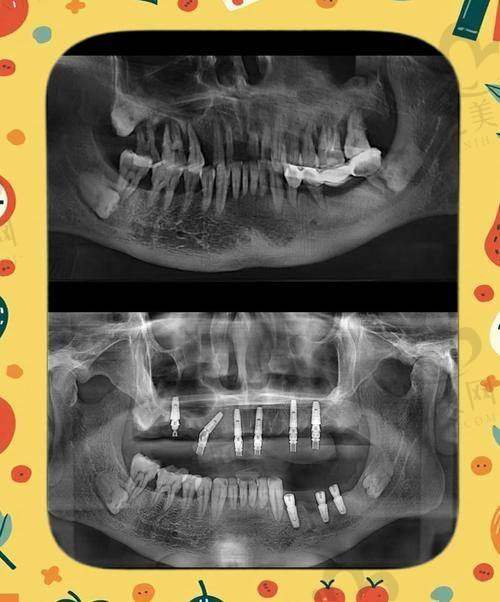

深圳正夫口腔总院位于南山区粤海街道海德一道88号中洲控股金融中 心A座5层(海岸城对面)。这里种植牙手术非常厉害,能够开展高难度穿颧穿翼种植。

在患者上颌骨骨量重度不足的情况下,通过颧骨和翼板区种植实现种植修复过程,整个种植过程不需要植骨,不用切开,出血量少,大大缩短了从种植到修复的周期,为患者节省了时间和费用。